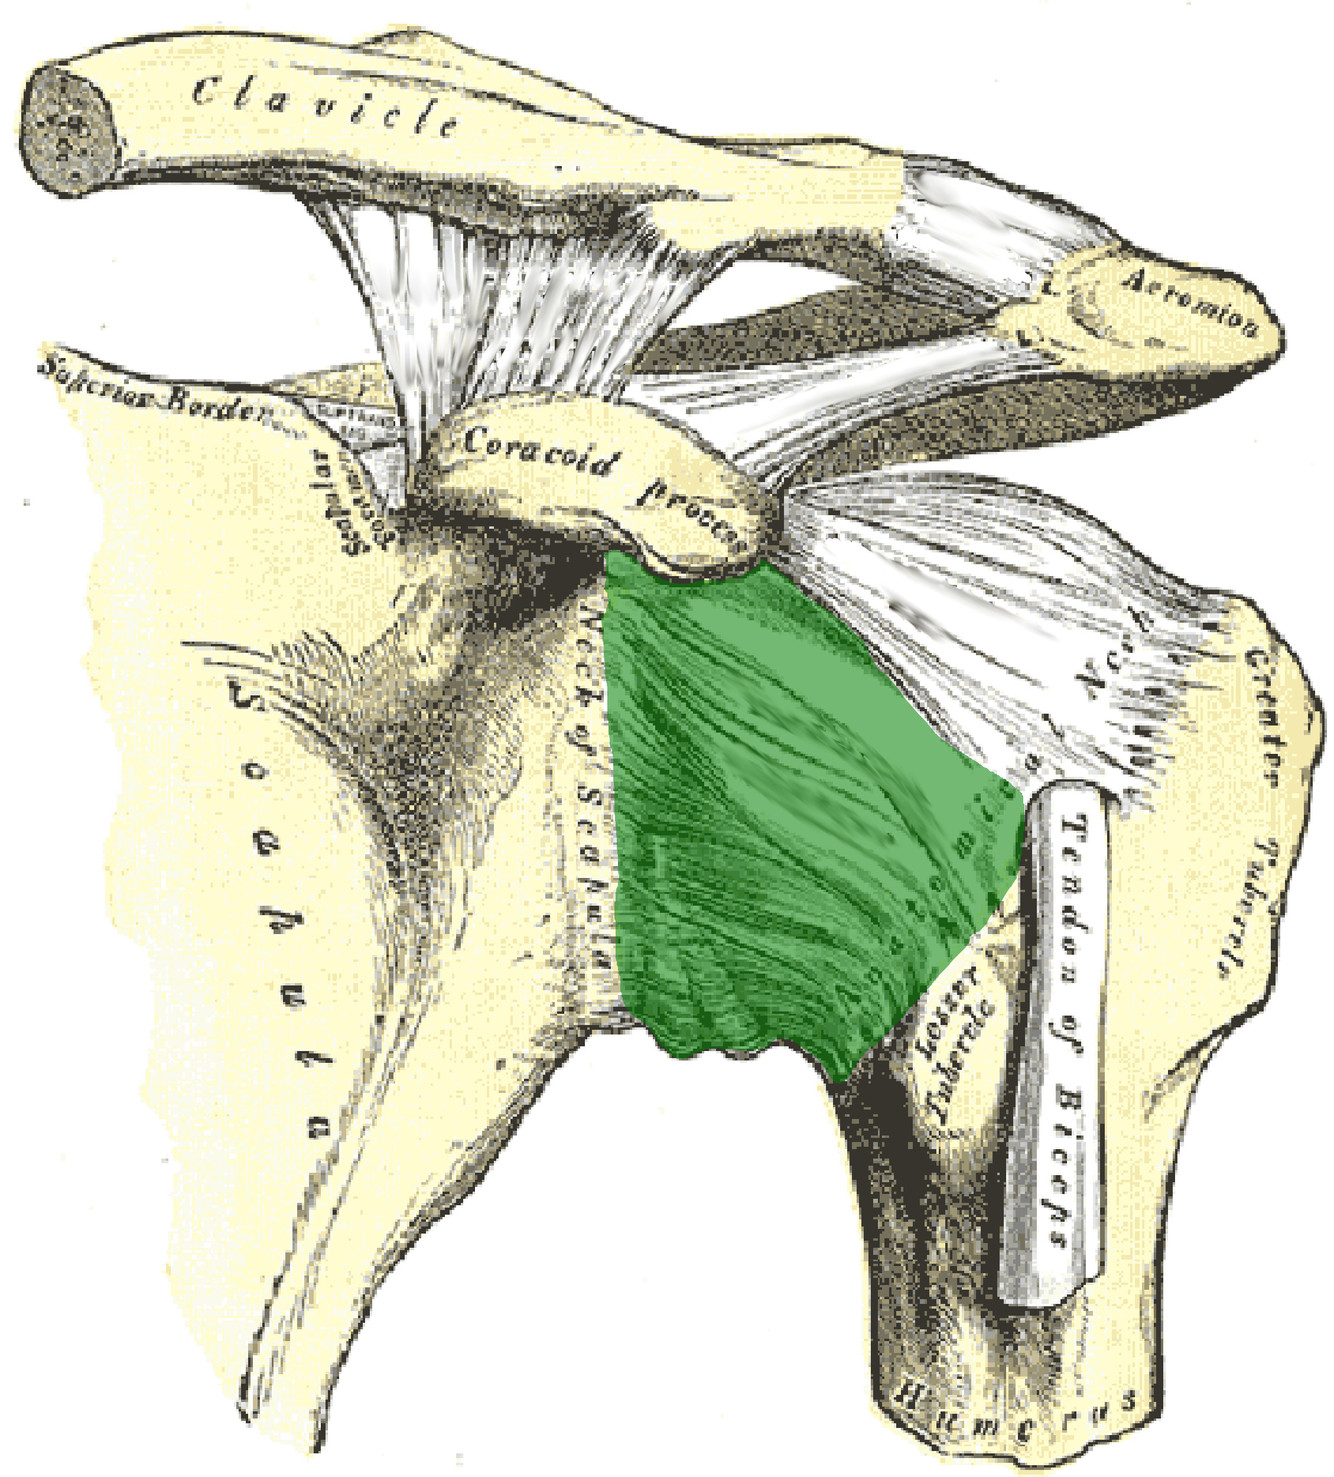

What is this structure?

Coracohumeral ligament of the shoulder